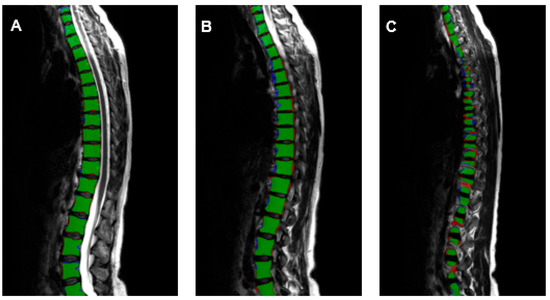

| VB | VD | SC | |

| Precision | 0.908 | 0.902 | 0.926 |

| Recall | 0.909 | 0.908 | 0.924 |

| Dice-score | 0.908 | 0.905 | 0.925 |